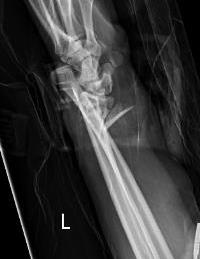

Techniques

Options

Styloid screw

Tension band wire

Ulna hook plate

Synthes distal ulna hook plate

AO surgery ulna styloid fracture screw fixation

AO surgery ulna styloid TBW fixation